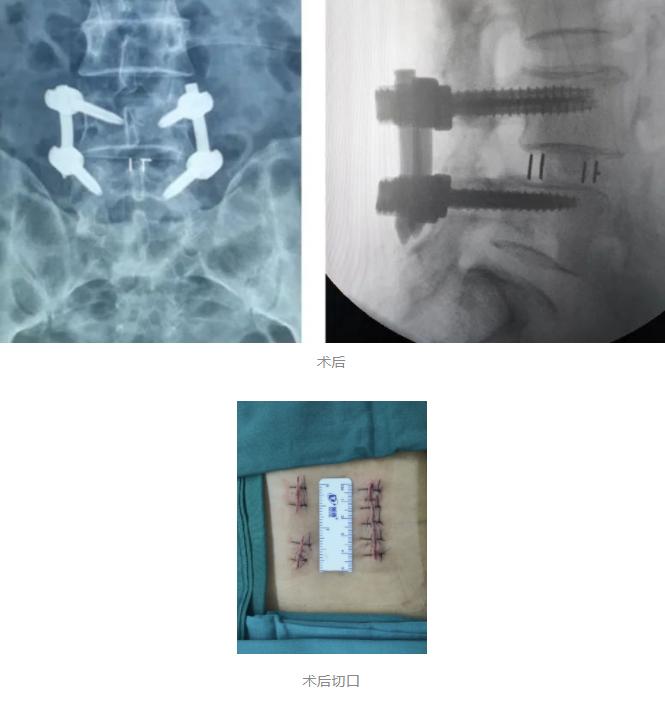

在骨科机器人+3D裸眼显微镜的辅助下,王阿姨的手术进行的很顺利,术中仅出血约50ml,而皮肤表面也只留下了3cm的小切口,这一切都与传统手术形成的极大对比!可以说,骨科机器人+3D裸眼显微镜在当今脊柱外科关于微创手术这一概念中,已成为一种趋势,其最大程度的保证了患者在术中的安全,将微创手术最为核心的精准、伤害小的特点发挥的淋漓尽致,这对于患者本身及术后的康复来说都极为有利!